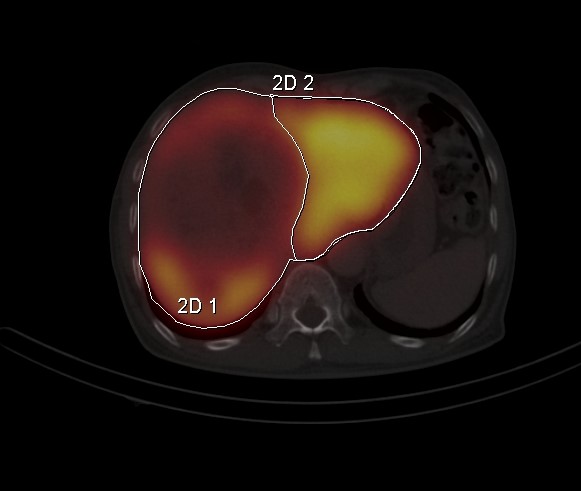

FLR

Liver FLR SPECT for resection